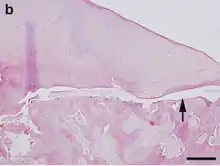

Hematoxylin and eosin staining. Bar = 200 μm.

OCD also is found in animals, and is of particular concern in horses, as there may be a hereditary component in some horse breeds.[97] Feeding for forced growth and selective breeding for increased size are also factors. OCD has also been studied in other animals—mainly dogs, especially the German Shepherd[98]—where it is a common primary cause of elbow dysplasia in medium-large breeds.[99]